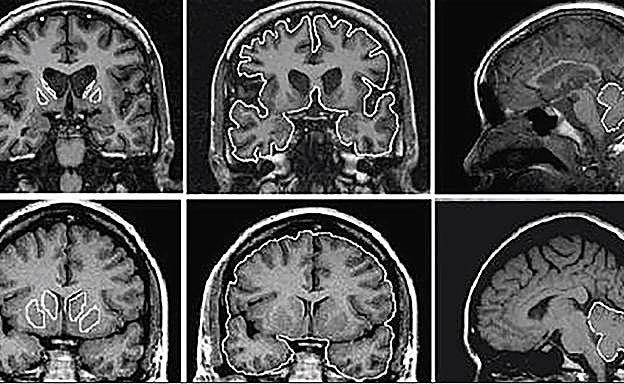

Imágenes de un cerebro afectado por la enfermedad de Huntington (arriba) y abajo, un cerebro sano. R.C.

La enfermedad de Huntington es un 'cóctel' agravado de las dos anteriores, ya que presenta todos sus síntomas y consecuencias, y además suma la afección neuromotora. El paciente sufre una pérdida de la capacidad intelectual y de las facultades emocionales y la falta de control sobre los movimientos. Esto convierte al huntington en una de las afecciones neurodegenerativas más devastadoras.

La enfermedad es causada por un error en una sección de ADN encargada de producir el gen huntington. Este es el responsable de la formación de la llamada huntingtina, una proteína que alimenta las células cerebrales. Sin embargo, en los pacientes que sufren la enfermedad, esta proteína se corrompe y en lugar de nutrir a las células, lo que hace es acabar con ellas. El nuevo fármaco se encarga de aislar ese error en el ADN, por lo que detiene el avance de la enfermedad.